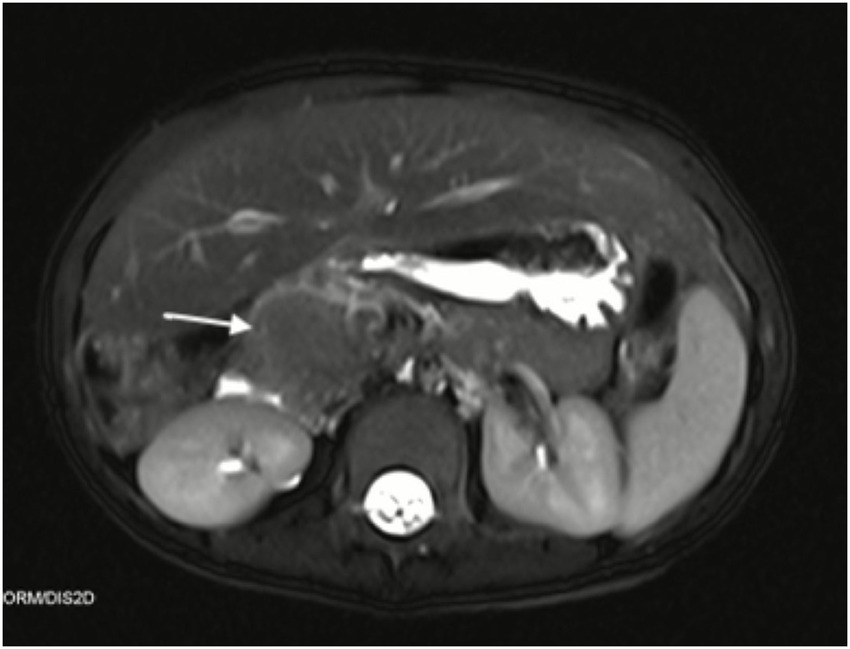

The patient, a 2-year-old girl, was suddenly found to have unusual ecchymosis on her feet. A pediatrician found that the platelet count of the child had decreased significantly, and the lowest platelet value was 4 × 109/L. The initial clinical diagnosis was primary immune thrombocytopenia, and the child was treated with gamma globulin and prednisone. When the child was 4 years old, she developed unexplained abdominal pain and the levels of liver enzymes suddenly increased. Enhanced MRI demonstrated an abnormal focus in the pancreatic head, measuring ~2.3 × 1.3 cm. The T2-weighted image revealed that the tumor showed a mild hypointense signal, and enhanced MRI showed inhomogeneous delayed enhancement of the mass (Figure 1). MRI demonstrated the invasive nature of the lesion, which appeared as a mass with extensive pancreatic involvement, extending to abut the right liver.

Figure 1

Axial T2-weighted and contrast-enhanced MRI of the abdomen demonstrating a mildly hypointense mass with inhomogeneous delayed enhancement.